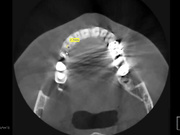

Секреты стоматологии с доктором Самвелом Блея

Категории: Стоматология